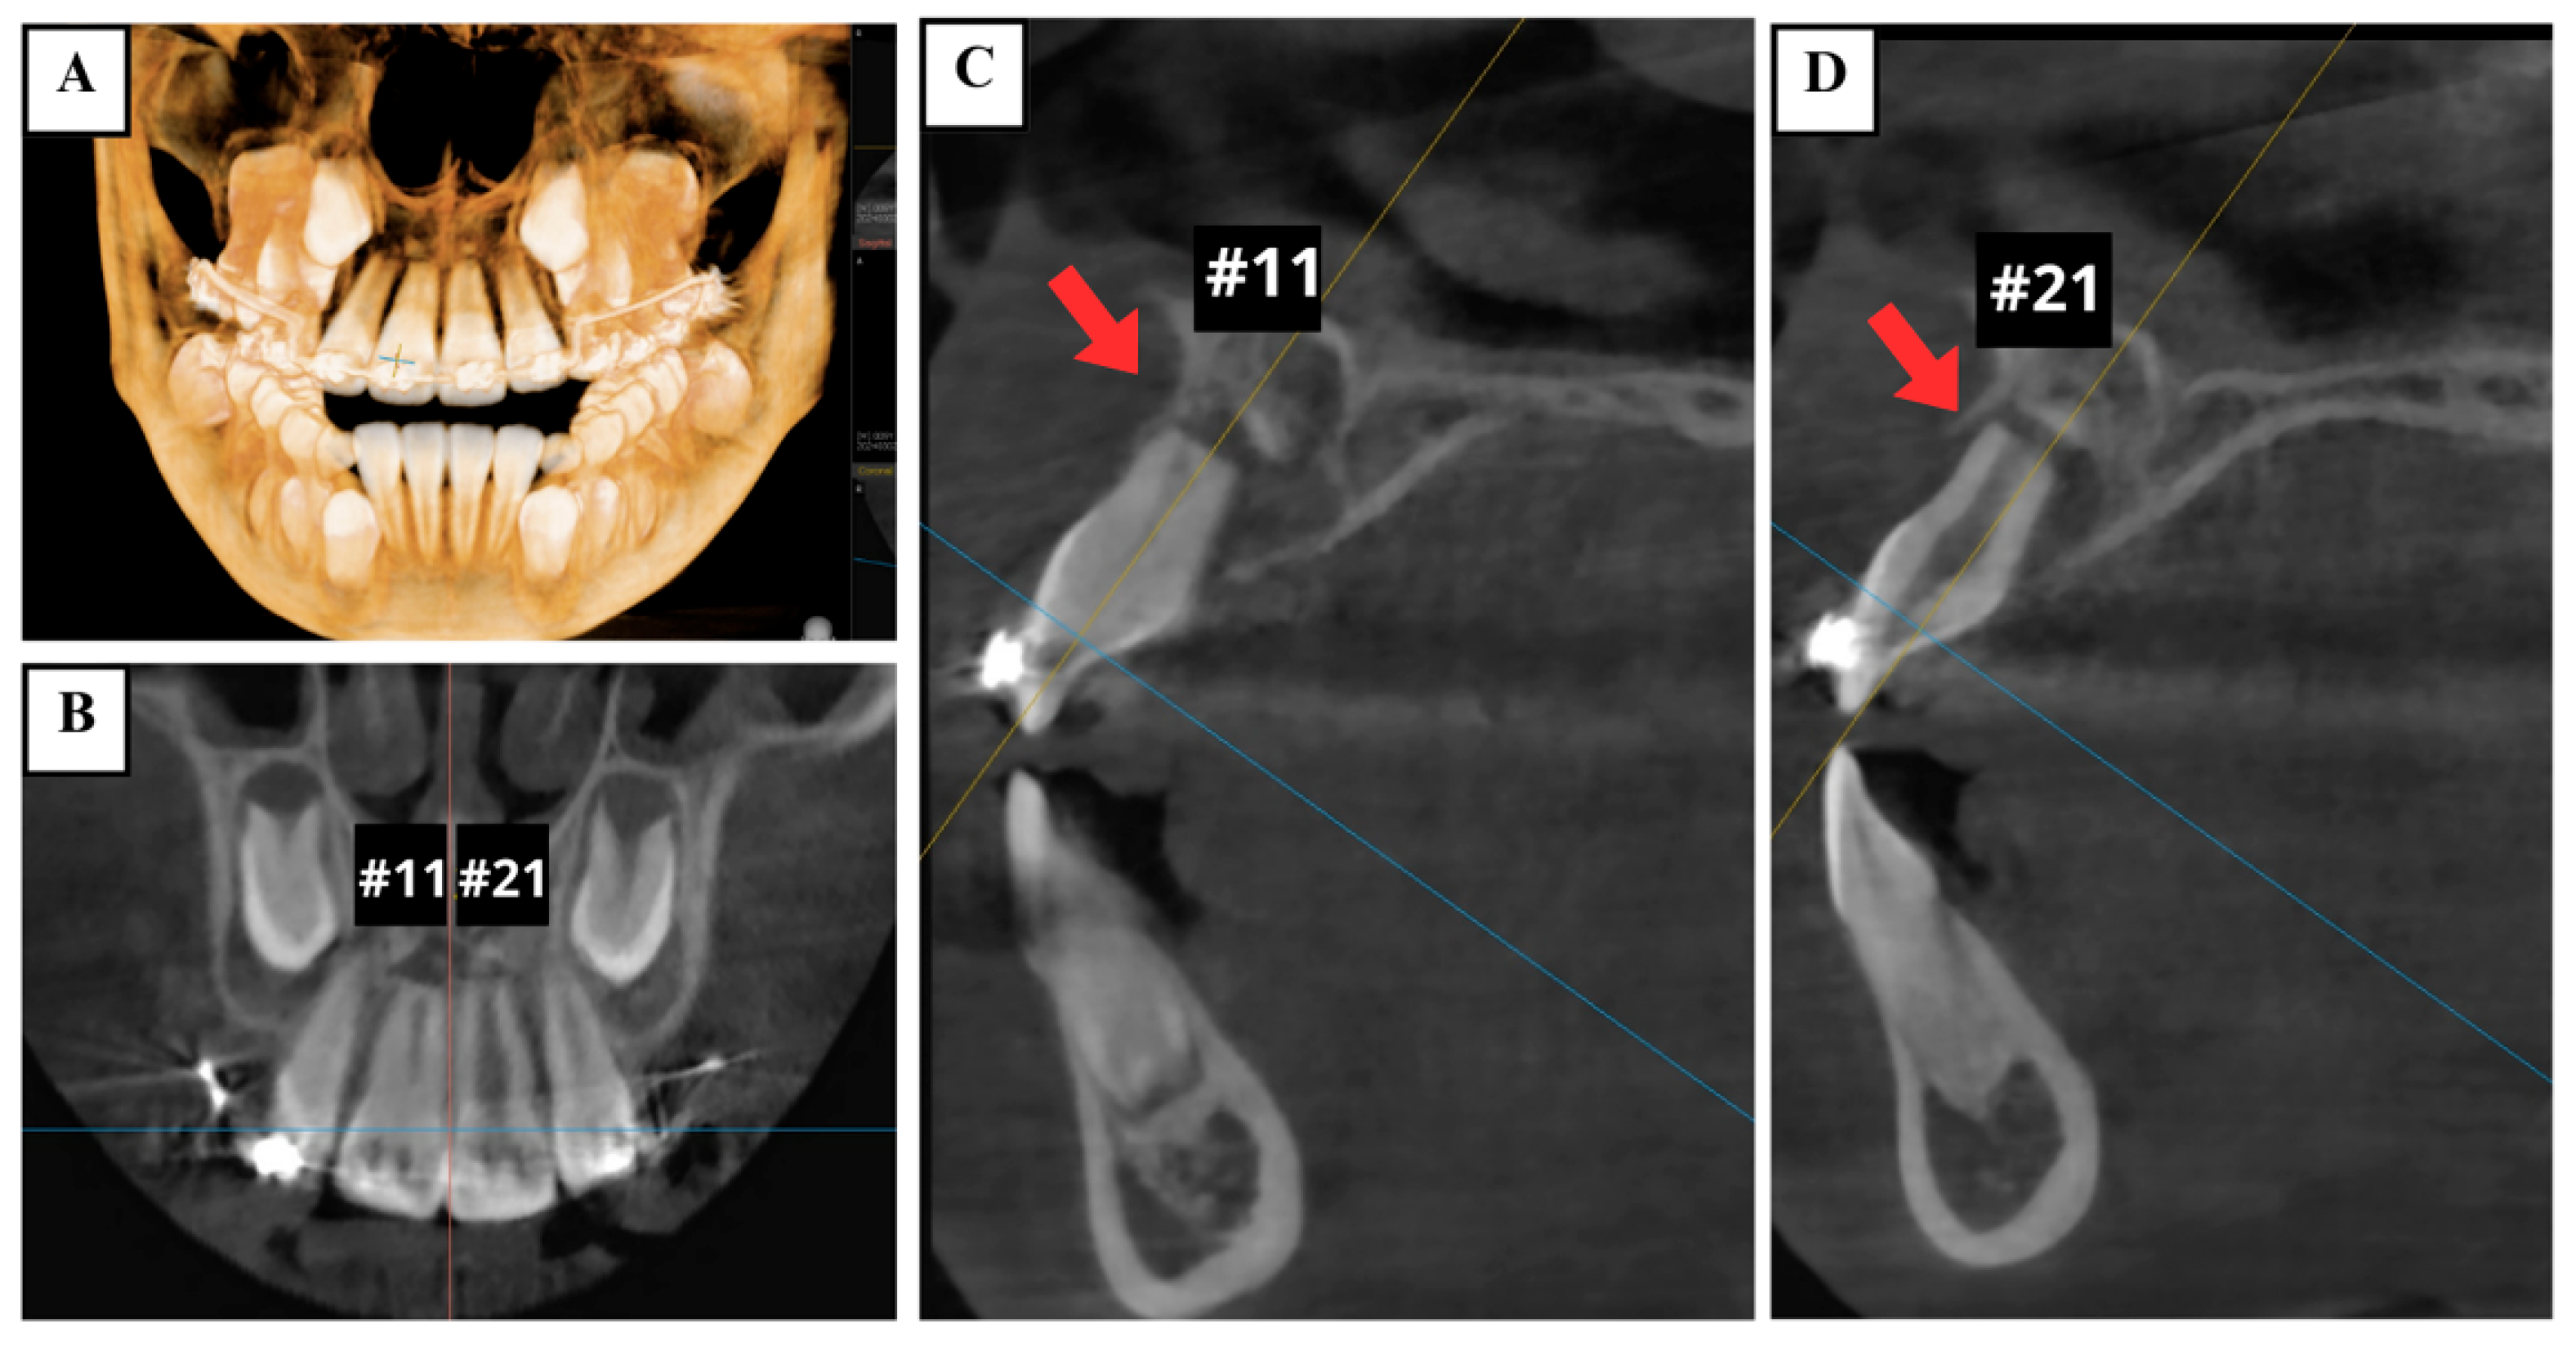

The anterior teeth were initially aligned to allow for more effective tooth movement later (Figure 4A). Once the teeth were properly aligned after 8 weeks (Figure 4B), the coronal fragments of teeth #11 and #21 were then repositioned and stabilized using a utility arch constructed from 0.016 × 0.022-inch blue Elgilol wire (Figure 4C,D). Fourteen months later, teeth #11 and #21 remained clinically asymptomatic. The extrusion of both teeth had been corrected to 0 mm, and mobility was close to normal (Figure 4E). At this time, EPT still showed positive results. Radiographs indicated satisfactory periodontal tissues around both of the fractured fragments and the apical area, without evident radiolucency of apical inflammation or root resorption seen on the CBCT (Figure 5).

Figure 5.

CBCT images at 14 months after orthodontic treatment showing satisfactory periodontal tissues around both the fractured fragments and the apical area (arrows). (A) 3D reconstruction. (B) Coronal view. Sagittal views of the (C) right maxillary central incisor (tooth #11) and (D) left maxillary central incisor (tooth #21).